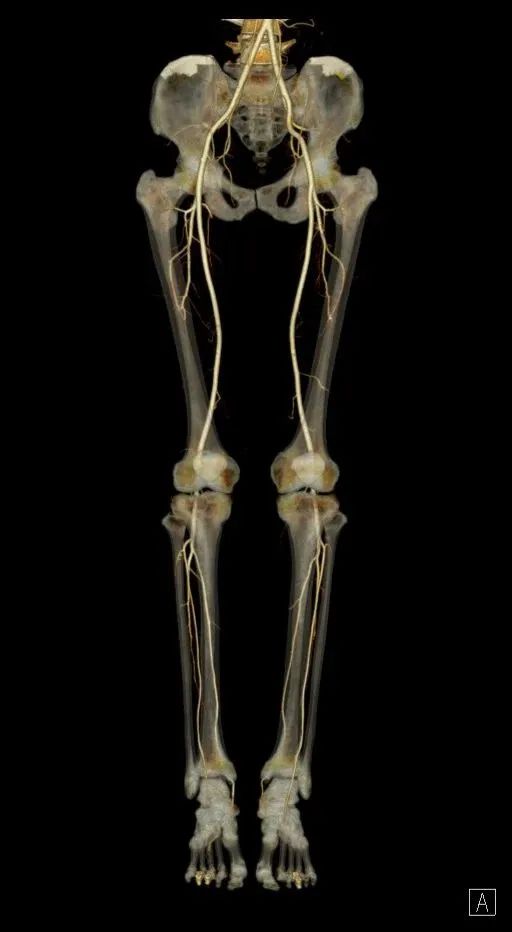

CT 血管造影(CTA),即 CT 血管成像,是一种利用计算机三维重建方法合成的非创伤性血管成像技术,可以在没有创伤的情况下,很好地了解身体中血管的情况。具有时间短、无创、特异性和敏感性高,时间和空间分辨率高等特点,能全方位显示出血管病灶,对于经其他检查已经明确患有血管疾病,需进一步了解病情严重程度具有重要的意义。

通过 CT 血管成像,可显示动脉病变,如血管闭塞、动脉瘤及夹层动脉瘤、血管畸形、血管损伤、心脏冠状动脉病变等。可进行冠心病 CT 筛查,冠心病术前、术后评估,脑卒中一站式检查,灌注成像等。

CT 血管造影(CTA)检查适用于动脉夹层、动脉瘤、不明原因出血、缺血性疾病、血管畸形、动脉栓塞、动脉硬化、动脉变异等血管疾病。

CTA 检查在大血管、外周血管疾病、心脏冠状动脉相关疾病、中枢神经系统疾病以及肿瘤疾病的诊断中发挥着重要作用。